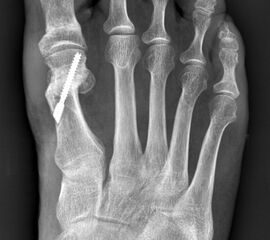

Die Akin-Osteotomie erfolgt in mindestens 50% begleitend zu metatarsalen Osteotomien im Rahmen der Korrektur einer Hallux valgus Deformität 12. Diese gehören zu den am häufigsten durchgeführten orthopädischen Eingriffen. Eine präzise Planung der notwendigen Korrektur unter Berücksichtigung aller Komponenten ist daher unabkömmlich. Dabei sollte eine Valgus-Deformität der Grundphalanx mitbehandelt werden, da diese die Entwicklung eines Rezidivs begünstigt. Die valgische Deformität der Grundphalanx mit veränderten Gelenksflächenwinkeln wird als Hallux valgus interphalangeus bezeichnet (Abb. 1). Dabei können verschiedene Winkel zur Definition der Fehlstellung angegeben werden (Abb. 2) 34. Bei der Beurteilung des Hallux valgus interphalangeus im Rahmen einer Hallux valgus Deformität ist zu beachten, daß häufig eine Hyperpronation der Grundphalanx besteht. Durch diese Malrotation werden die eigentlichen pathoanatomischen Winkel "verprojiziert". Am Röntgenbild erscheinen diese projizierten kleiner als die reellen Winkel. Somit sollte intraoperativ nach einer metatarsalen Osteotomie überprüft werden, ob eine Restfehlstellung im Sinne eines Hallus valgus interphalangeus besteht, da das präoperative Röntgenbild die Fehlstellung nicht immer exakt abbildet.

• Hallux valgus interphalangeus (Abb.1, Abb.2, Abb.3).

• Röntgenaufnahme des Fußes (unter Belastung) in dorsoplantarem und seitlichen Strahlengang (Abb. 3) und präoperative Fotodokumentation.

• Beurteilung des proximalen Gelenkflächenwinkels der Grundphalanx (Proximal Phalangeal Articular Angle, PPAA) des Hallux valgus interphalangeuswinkels (Hallux interphalangeus Angle, HIA) sowie des proximalen zum distalen Gelenksflächenwinkel (Proximal to Distal Phalangeal Articular Angle, PDPAA) 6789 (Abb. 2).